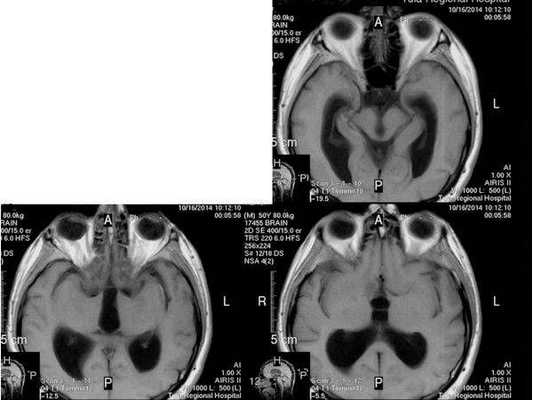

По заключению МРТ от 14.05.2013, после операции в левом полушарии мозжечка появились кистозно-глиозные изменения (на месте повреждённых нейронов образовались рубцовая ткань), а также выраженная внутренняя асимметричная гидроцефалия (избыточное скопление спинномозговой жидкости в полости черепа).

- МРТ в динамике показывает постепенное сужение желудочковой системы на 2 мм. Для сравнения представлены снимки МРТ от 14.05.2013 и от 16.10.2014.